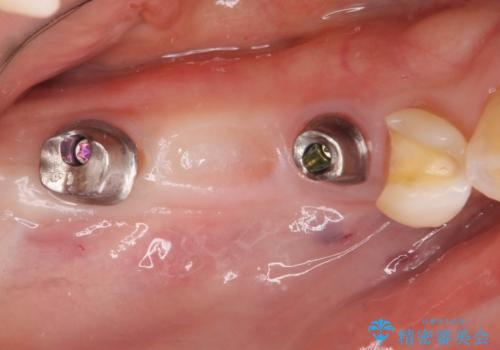

失った奥歯をインプラントで機能回復

- 3本失った奥歯の機能回復するために、インプラント治療を希望され来院されました。

よりしっかりと噛むことのできるインプラントによる治療を進めていくこととなりました。

- 110万円(インプラント×2・チタンカスタムアバットメント×2・ジルコニアクラウン×3・仮歯×3)費用は治療当時の料金となります